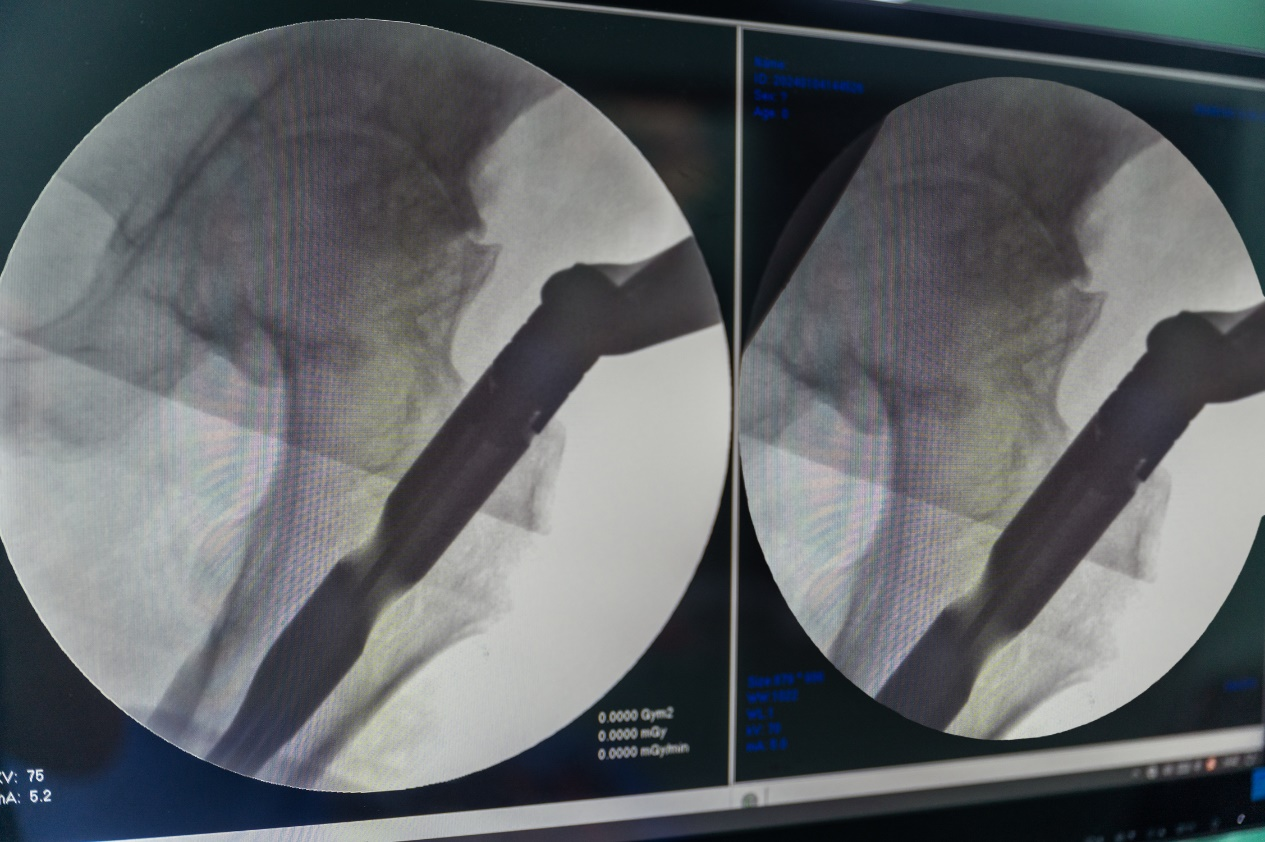

5.透视复位,观察复位情况

6.调节牵引力与方向,X线透视骨折短缩畸形纠正。

7.牵引下钢丝环扎纠正侧方移位,X线透视解剖复位